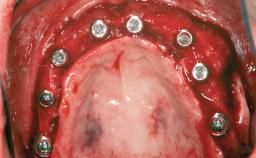

Le Fort I Interpositional Graft and Mandibular Sandwich Osteotomy for Maxillofacial Rehabilitation after Severe Periodontitis

A 47-year-old woman who had suffered from aggressive periodontitis requiring a number of periodontal interventions over more than 10 years was referred by her general dental practitioner and periodontologist for bone augmentation and implant therapy. Her failing dentition had already been scheduled for extraction. The patient expressed a desire for implant-supported fixed restorations and esthetic improvement of her lower face. She had agreed to consult with a maxillofacial surgeon after the referring dentist had suggested bone augmentation. An initial examination by the maxillofacial surgeon revealed mobility of all residual teeth in a patient who was very unhappy with the function of her removable partial dentures. Due to periodontally migrated flaring teeth and loss of occlusal support, the vertical dimension of occlusion was dramatically reduced. The patient was displeased with her lower face because of deepened nasolabial, commissural, and supramental folds.

# of Implants 14

Bone Augmentation Horizontal|Sinus Floor Elevation|Staged|Vertical